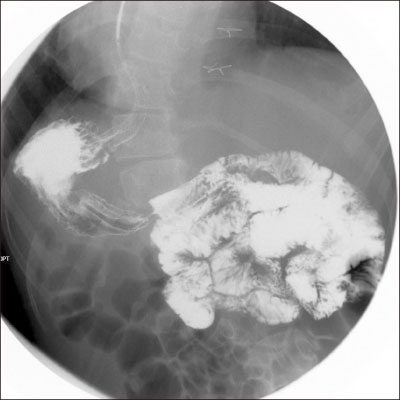

Fig. 3). Proximal transverse colon was redundant and upstream dilatation from the twisted transverse colon to the ascending colon and the cecum was found with reversed intestinal anatomy, as identified on preoperative images. Sigmoid colon was collapsed and not redundant, so the suspicious sites of endoscopy were not related to the symptoms. Adhesiolysis and fibrous band lysis between the transverse colon and adherent soft tissue was done. Redundant proximal transverse colon was resected via mini-laparotomy site, and end-to-end colocolic anastomosis was performed (

Fig. 4). There was no postoperative event, and the patient was discharged without complications.

Fig. 4Resected redundant transverse colon.